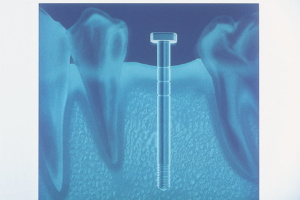

The BASIC implant used in this case is a self-tapping stage-one implant that is screwed into place with a simple ratchet. This particular implant system is unique because it utilizes a hex-recess hole that accommodates resin cementable customized posts and cores.3 Because this particular protocol is so quick, simple, and conservative, it is possible to obtain impression records of the implant site and the opposing arch at the time of surgery. Thirty minutes is more than adequate time required to perform this phase of the implant treatment ( Figure 5).

The spatial position of the implant was obtained by simply seating the implant position transfer device (IPTD) into the implant and impressing with polyvinylsiloxane impression material (Figures 7 and 8). The IPTD does not usually dislodge when the impression is unseated because of its tight fit in the implant. The IPTD was simply indexed back into the set impression with the analog fully seated onto the stem (Figure 9). Cyanoacrylate was flowed into the IPTD analog and the impression to eliminate possible movement during transportation to the lab and pouring of the working model. The working model with the analog precisely embedded was now ready for prosthetic fabrication (Figure 10). BASIC's unique prefabricated post-core is designed to allow core customization, up to 20º from the long axis, by simply cutting it back as desired with a dental drill (Figure 11).